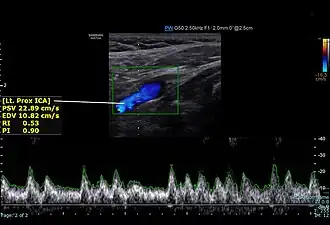

![]() Screenshot of a normal proximal internal carotid artery spectral Doppler | |

Doppler ultrasound allows for assessment of carotid arterial blood flow. Blood flow velocity is increased in areas of stenosis compared to normal. Therefore, doppler imaging substantially aids in the diagnosis of carotid artery stenosis by ultrasound.[2] Internal carotid artery (ICA) is located posterolateral, and larger when compared to the external carotid artery (ECA). ICA has low resistive pattern (difference between the blood velocities during heart systole and diastole) when compared to ECA.[3] ICA has sudden increase in velocity of blood flow during systole and persistent forward blood flow during diastole.[5][6] ICA peak systolic velocity more than 125m/sec and diastolic velocity more than 40 m/sec signifies stenosis.[3]